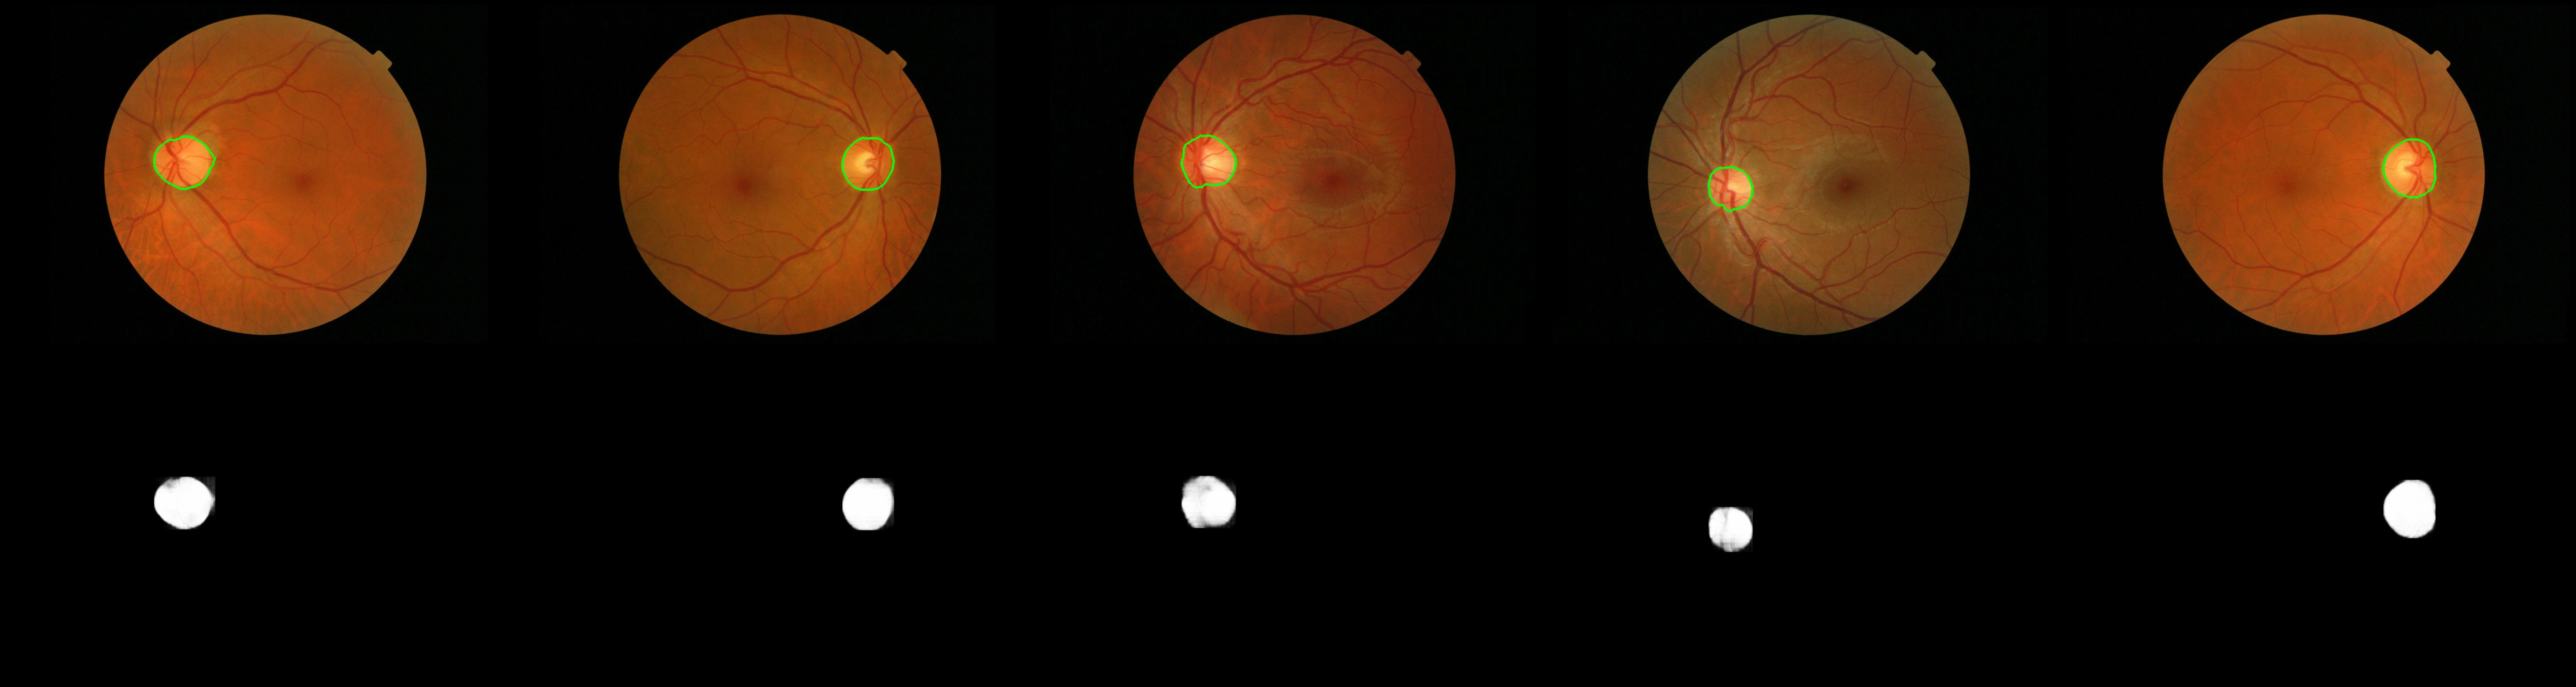

The performance of our model on Messidor-dataset:

When directly use unet model, we often get some error predictions. So I use a post-process algorithm:

- predicted area can't be to small.

- minimum bounding rectangle's height/width or width/height should be in 0.45~2.5

lefted area is the final output. The problem of this algorithm is that the parameters not self-adjusting, so you have to change them if input image is larger or smaller than before.